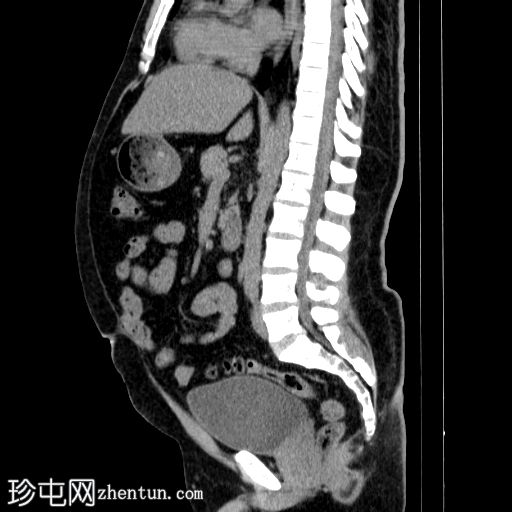

矢状位

平扫

左肾盂及肾盏系统内可见多发边界清晰的高密度结石,最大直径约2 cm,平均CT值约418 HU。

结石呈典型的球形形态。

左肾盏系统及肾盂轻度扩张至肾盂输尿管连接处,提示肾盂输尿管连接处梗阻,但未见输尿管扩张或肾周脂肪浸润。

影像学表现符合左肾结石的诊断,与患者的左肾绞痛症状相符。未见输尿管扩张或肾周脂肪间隙增厚,提示本次发作可能并非由急性输尿管梗阻引起。

左肾肾盂肾盏系统轻度扩张至肾盂输尿管连接处,提示可能存在肾盂输尿管连接处梗阻,该梗阻可能导致肾盂输尿管连接处梗阻,进而造成左肾多发性结石形成。